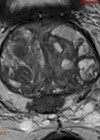

Case 1 A 67-year-old gentleman underwent a CT scan after presenting with visible haematuria and weight loss. His comorbidities include hypertension, type II diabetes mellitis and hypercholesterolaemia. He is a smoker. Figure 1. Figure 2. What do Figures 1 and...